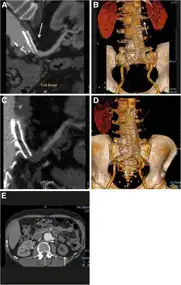

Diagram of renal artery stenosis

Renal artery stenosis (RAS) is the narrowing of one or both of the arteries to the kidneys.[3] Early on there are typically no symptoms, while later high blood pressure or kidney problems may occur.[3] The blood pressure may be difficult to treat.[2] Complications may include chronic kidney disease, stroke, and coronary artery disease.[3]

About 90% of cases are due to atherosclerosis.[3] Other causes include fibromuscular dysplasia, vasculitis, AAA, and arterial dissection.[3][2] Risk factors for atherosclerosis include high cholesterol, smoking, diabetes, high blood pressure, obesity, inactivity, and family history.[3] Diagnosis is generally by ultrasound or CT scan.[2]

Diagnosis

The diagnosis of renal artery stenosis can use many techniques to determine if the condition is present, a clinical prediction rule is available to guide diagnosis.[10]